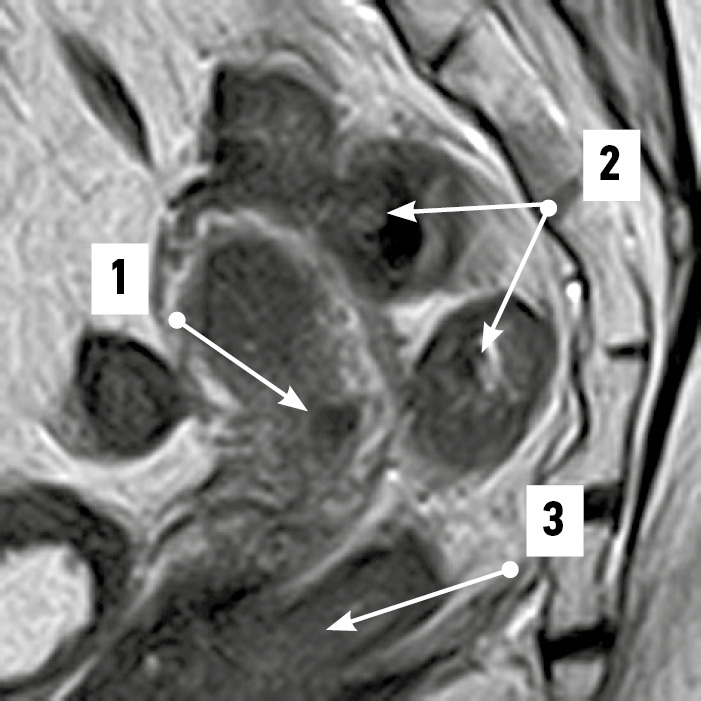

При положениях dextrodeviatio uteri на уровне надвлагалищного участка прямой кишки в 75% случаев крестцовый изгиб кишки в сагиттальной плоскости сочетался с изгибами во фронтальной плоскости (рис. 7). Ещё в 25% случаев определялся сагиттальный изгиб, соответствующий тазовой поверхности крестца. Среднее расстояние от матки до прямой кишки в надвлагалищном участке соответствовало 5,56±0,66 мм. Разброс величин составил 2,97–11,4 мм.

Рис. 7. Извитой во фронтальной плоскости надвлагалищный участок прямой кишки. Магнитно-резонансная томограмма органов таза в режиме SG T2: 1 — матка; 2 — надвлагалищный участок прямой кишки (извит во фронтальной плоскости); 3 — влагалищный участок прямой кишки. / Fig. 7. Supravaginal portion of the rectum convoluted in the frontal plane. SG T2-magnetic resonance imaging of the pelvic organs: 1 — uterus; 2 — supravaginal segment of the rectum (convoluted in the frontal plane); 3 — vaginal segment of the rectum.